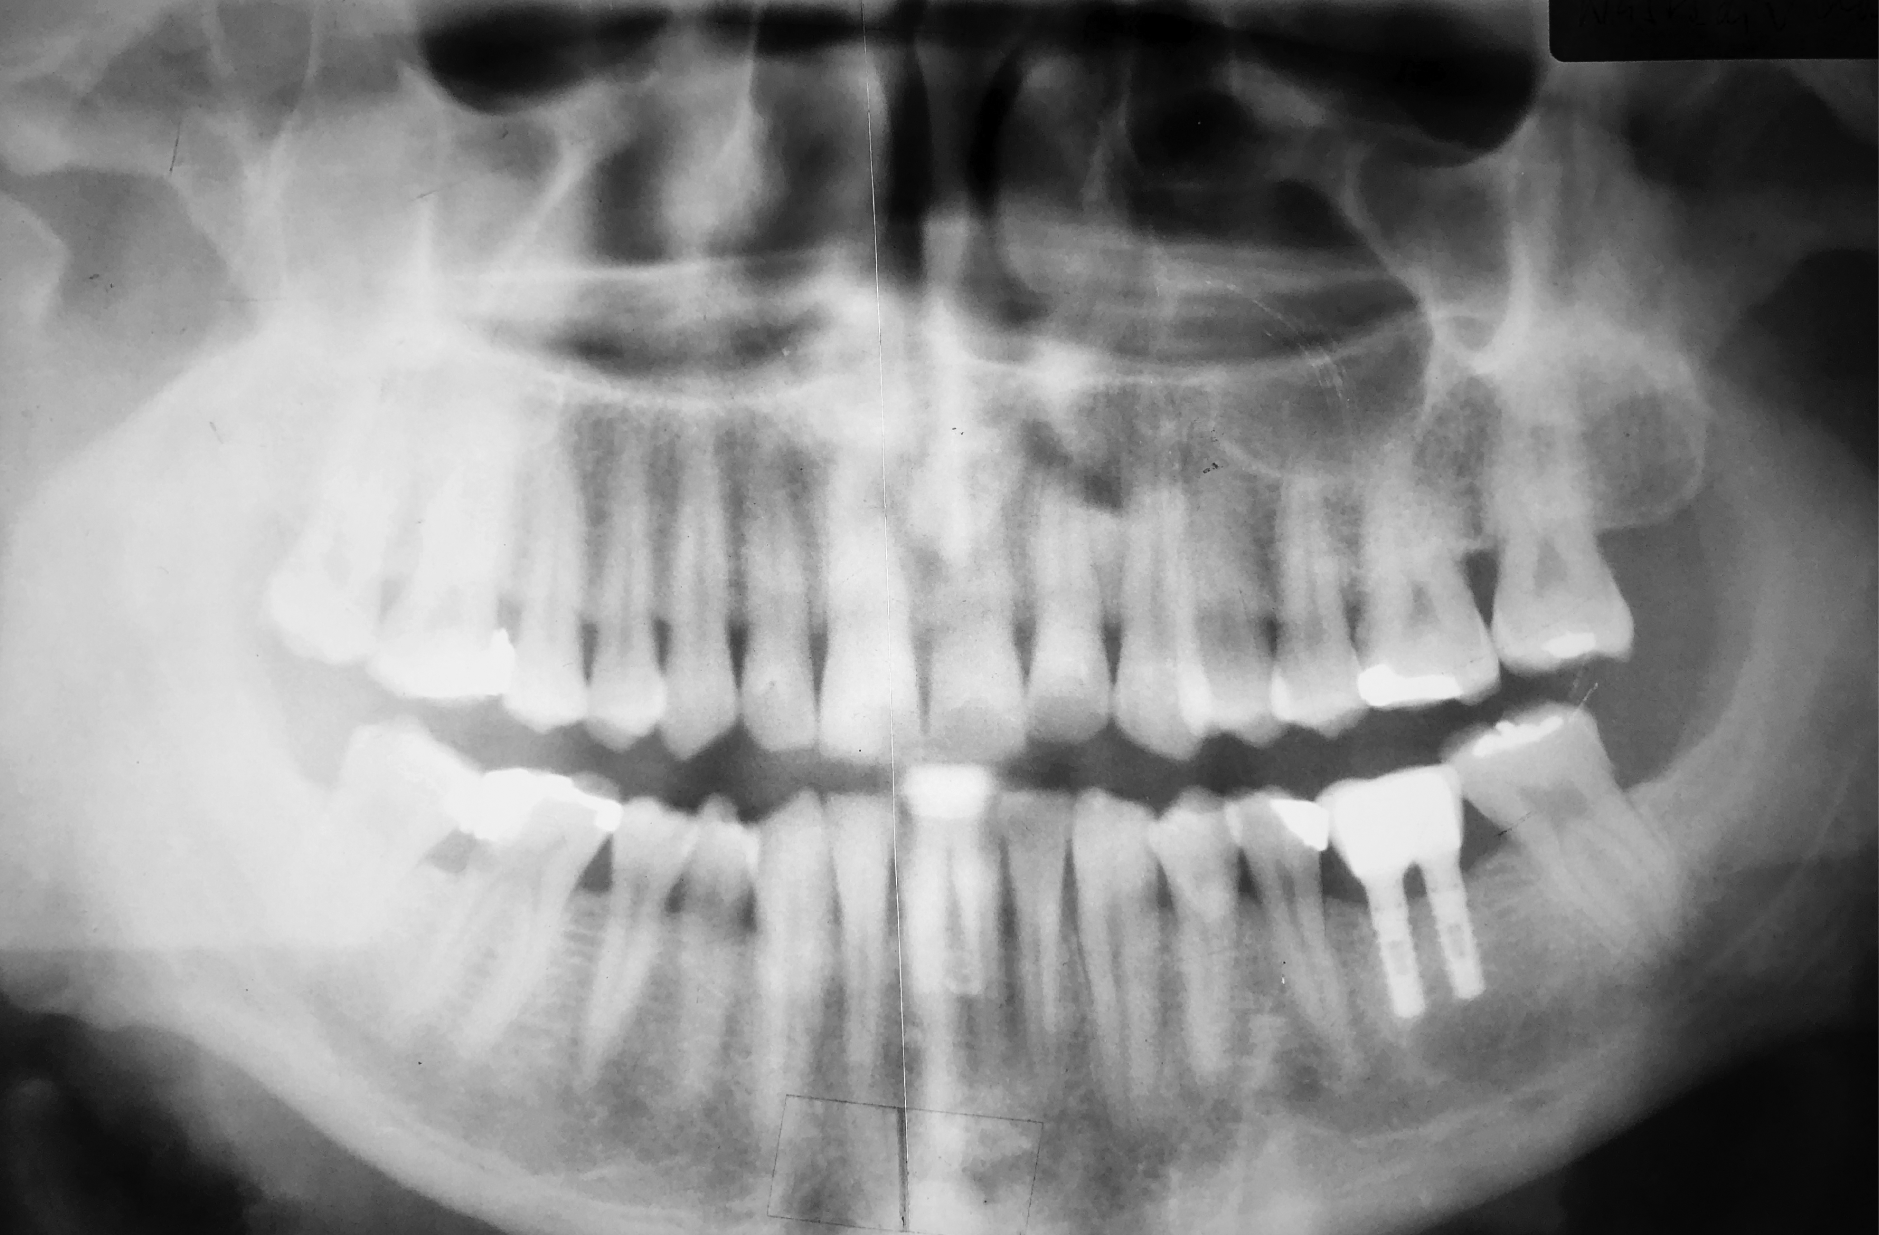

Bei dem Recall im April 2013, nach 10 Jahren in Funktion, war die Versorgung weiterhin perfekt funktionsfähig und die Gewebe um die Implantate waren gesund.

Röntgenaufnahme aus dem Recall im März 2024. Nach 21 Jahren in Funktion wurde die Versorgung neu gestaltet. Die Implantate waren stabil und das klinische Bild ohne Befund. Die Resorption aufgrund der Kontrollaufnahme war 0 mm.